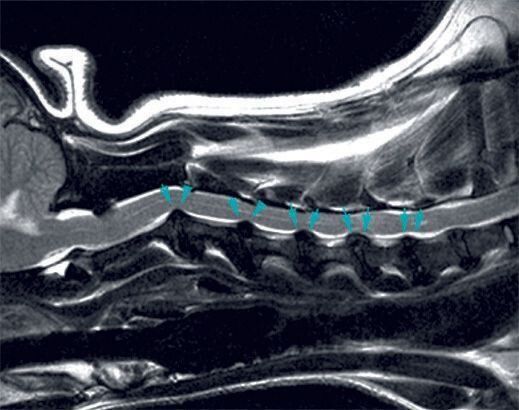

よく聞くけれど意外に知らない⁉ 椎間板ヘルニアの治療や予防策を解説